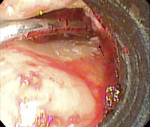

While the small incisions and minimal tissue reflection contributed to the superior results obtained using these techniques, visualization remained a primary limiting factor of MIS until the recent introduction of the videoscope (MicroSight, Q-Optics Inc, www.q-optics.com) described by Harrel et al. The videoscope is a high-definition digital camera placed on the end of a flexible tube 2.7 mm in diameter featuring a carbon fiber retractor that may be rotated to aid in flap reflection and a gas-shield that prevents blood and contamination from obscuring the camera, allowing improved visualization of the defect once inserted into the surgical site. Images taken with the videoscope are seen on a nearby surgical monitor at 20X to 60X magnification (Figure 12). Clinically, the enhanced visualization achieved with the videoscope facilitates improved defect debridement and root planing.10 Figure 13 shows the hand piece containing the videoscope that is used during surgery. A sample case treated with the videoscope and MIS (ie, VMIS) can be seen in Figure 1 through Figure 11.

To highlight the capabilities of VMIS, Harrel et al15 presented a clinical outcomes case series that featured an original cohort of 30 patients with 110 qualifying sites treated with VMIS and followed for at least 36 months. For inclusion, patients had an isolated interproximal area of periodontal destruction with a PD of at least 5 mm, CAL of at least 2 mm, and radiographic evidence of bone loss on periapical radiographs following initial nonsurgical therapy. The authors obtained minimally invasive surgical access, debrided the sites and planed the roots, biomodified root surfaces with 24% EDTA, and grafted with EMD and DFDBA. As before, flaps were repositioned and sutured while closure was ensured by digital pressure applied to the papilla tips with moist sterile gauze. Clinical measurements were recorded at baseline, 6 months, 12 months, and at least 36 months post-operatively. All 30 patients were available for the 6-month data, 18 patients were available for the 12-month data, and 14 patients were available for the 36-month or greater data, with an average post-operative time of 46.5 months ranging from 36 to 58 months. Since no statistically significant difference was found between measurements obtained for 1-wall, 2-wall, and 3-wall defects, data was combined for patient-level measurements of all surgical sites for the 14 patients who completed the study through the final evaluation. Results for these 14 patients revealed that a mean baseline PD of 6.41 ± 0.66 mm improved to 2.81 ± 0.58 mm at 6 months, 2.18 ± 0.58 mm at 12 months, and 2.61 ± 0.88 mm at 36 months+ for a mean improvement from baseline to 36 months+ of 3.80 ± 1.18 mm (P < 0.001). Measurements for gingival recession revealed that a mean gingival recession at baseline of 0.74 ± 0.95 mm improved to 0.69 ± 0.98 mm at 6 months, 0.31 ± 0.39 mm at 12 months, and 0.38 ± 0.67 mm at 36 months+ for a mean improvement (ie, gain in soft tissue height) of 0.36 ± 0.64 mm (P = 0.057) from baseline to the final post-operative visit. Finally, measurements for CAL improved from a mean baseline of 7.14 ± 0.97 mm to 3.50 ± 1.15 mm at 6 months, 2.49 ± 0.62 mm at 12 months, and 2.99 ± 1.05 mm at the 36 months+ post-operative for a mean improvement of 4.16 ± 1.18 mm (P < 0.001) from baseline to the final post-operative evaluation. Results of a visual analogue scale (VAS) patient survey indicated that only one patient experienced minor pain on the day of surgery while a different patient noted minor pain at the one and two week post-operative visits. All other patients reported no pain on the day of surgery or at any of the subsequent appointments.15 Additionally, all patients were satisfied with their treatment and said they would undergo the procedure again if indicated and would recommend the treatment to a friend.17 The results of the VAS survey highlighted one of the most important advantages to MIS, namely that patients generally experience minimal to no discomfort and have a high degree of satisfaction with the procedure.